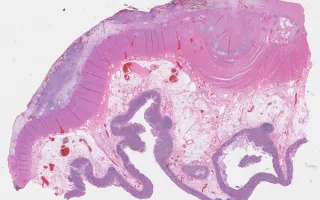

Patient presented with acute appendicitis and perforation. An appendectomy was performed (see Related Content), and the patient was followed. A subsequent recurrence of disease occurred necessitating surgical resection of the colon (this specimen.)

This case represents a goblet cell carcinoid that has recurred and is now invasive within the wall of the colon (this slide). Conventional-type adenocarcinoma has also arisen within the goblet-cell carcinoid (“adenocarcinoma ex goblet-cell carcinoid” or mixed carcinoid-adenocarcinoma). This H&E slide highlights the conventional adenocarcinoma component.

Well-differentiated neuroendocrine tumours (“carcinoids”) of the appendix are usually found incidentally at appendectomy. When large or not confined to the tip, they can cause obstructive symptoms and/or appendicitis. Although uncommon, they account for a majority of appendiceal tumours. They are considered tumours of uncertain malignant potential. Goblet-cell carcinoid is a variant that shows both glandular and endocrine differentiation, with cells resembling normal intestinal goblet cells. Goblet-cell carcinoid is more aggressive than conventional carcinoids.

The prior appendiceal tumour was stained for EMA (LMP99001) and Alcian Blue (LMP63103), highlighting the presence of epithelial differentiation and mucin production, respectively. The original H&E slide is also linked (LMP28939) - see Related Content.

Four years later, the patient developed recurrent disease in which a malignant component was identified. A right hemicolectomy was performed, showing both a goblet-cell carcinoid (LMP26556) and invasive adenocarcinoma component (this slide). See also: Alcian Blue stain (LMP84148) in Related Content.